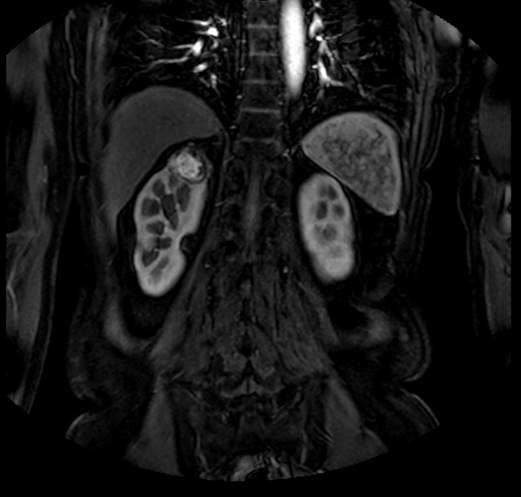

Laboratory workup reported a hemoglobin of 12 mg/dL (12-15.5 mg/dL), Urinalysis demonstrated microscopic hematuria with 10 rbc/hpf, and urinary metanephrines 0.3 (> 1.3 positive test). Magnetic Resonance (Figure 1 and 2) showed two ipsilateral renal tumors, one at the upper pole of 3.5 cm and the other at the mid-portion of the kidney of 3 cm, likewise an adrenal tumor of 1.5 cm was observed, normal chest x-ray.